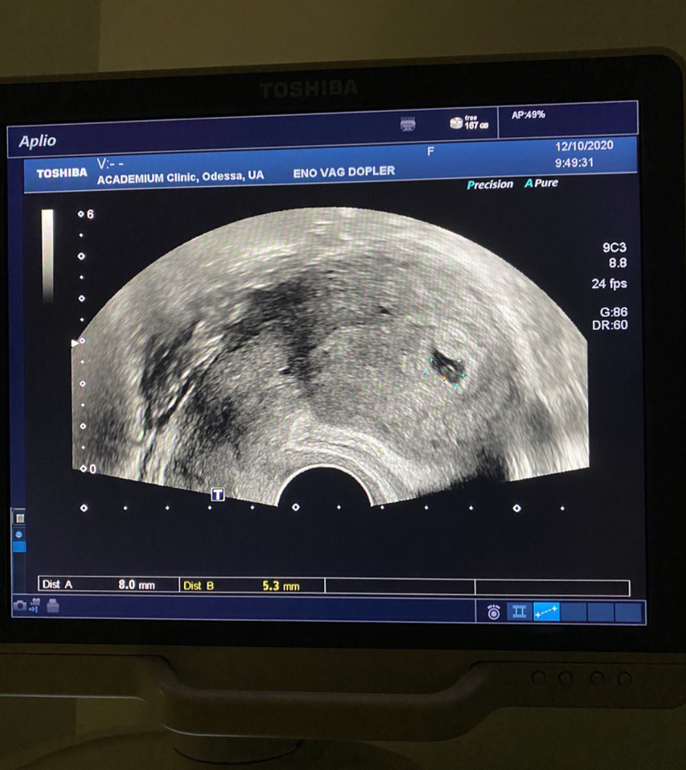

УЗИ

Сходила на УЗИ.

Какая красота! Здоровья вам 🤞🏻🙏🏻 А это какой срок?